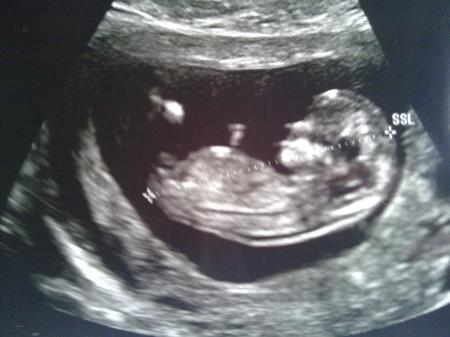

also der morgen fing heute recht früh an.meine beste freundin arbeitet wieder an einem tag und ich nehme den kleinen.also musste der kleine mann mit.mein mann war komisch angespannt(sonst ist er immer recht emotionslos)...kurze warterei und dann rein zu mc dreamy..:-) us übern bauch ging sagte er und dann : WAHNSINN...ich hab das noch "nie" (in der form und größe) gesehen...das herz schlug...die ärmchen bewegten sich und ich fing an zu weinen-wie jetzt auch wieder.toll....:-) ich war schon eine sehr lange zeit nicht mehr so glücklich.mich hat gerade ein riesiger kopf glücklich gemacht.lach.... das muß mutterliebe sein....ich versuche gleich mal das foto auf den pc zu ziehen und hänge es gleich an. mein mann war so überwältigt-selbst er hatte tränen in den augen und all die last fiel von uns ab..all die angst...die sorgen.... UNSEREM BABY geht es gut....ich bin überwältigt und wahnsinnig glücklich. danke fürs daumendrücken und all die lieben worte. kussi an euch alle

so...naja da sieht das kleine schätzchen komisch aus,aber das wird ja noch. ich liebe das mäuschen soooooo sehr. lg

Bild zu

unser schatz ist stolze 5,6 cm groß -ssl also mit beinen kommt noch was dran...lach hat sich fein gestreckt....oh das war so toll..oh nein,ich heul schon wieder-also jetzt reichts auch.lol

Ich hoffe wirklich das der Kopf dich glücklich gemacht hat und nicht wieder der Hintern :D

jetzt wo du es sagst:ist es wirklich der kopf???:-D